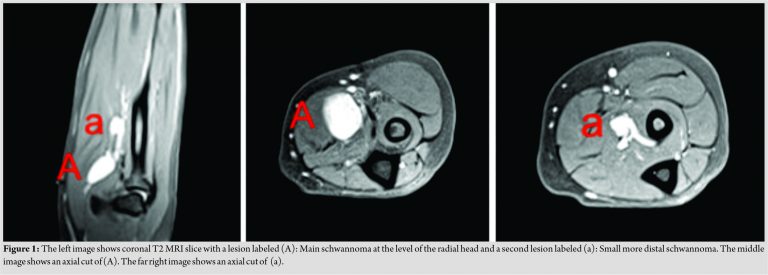

Schwannomas are solitary peripheral nerve tumors. They can also form a group of contiguous lesions when part of a systemic pathology such as NF 2 and/or schwannomatosis [3,4]. Nonetheless, a handful of cases reported previously in the literature which depicted multiple schwannomas encapsulating a single peripheral nerve with no associated systemic pathology [8]. Aslam et al. reviewed the literature from 1970 to 2000 and found only 14 reports similar cases depicting the rarity of this presentation. Therefore, they must be considered on the differential diagnosis during the pre-operative evaluation. Our case highlights the importance of the physical examination combined with the utility of advanced imaging. These lesions, though affecting the same nerve, typically are not the same size. Therefore, smaller lesions can be missed on physical examination as they tend to be difficult to palpate relative to their size. MRI is an important diagnostic tool and frequently employed to localize these masses. MRI can be used to better characterize the main lesion but can also be employed to investigate additional lesions adjacent or involving the same compartment, as was reported in the literature [4]. This will increase the likelihood of identifying multiple schwannomas in the upper extremity. The radiographic features of our case were similar to what previously reported regarding multiple schwannomas [10,11]. The MRI study showed an eccentric mass with an enhanced signal on T2-weighted images and reduced signal on T1-weighted images (Fig. 1). The histology of these tumors tends to show a positive S-100 protein marker that is commonly associated with schwannoma and typically organized in two clusters, Antoni A and Antoni B. These clusters help distinguish schwannoma from neurofibroma which tends to be less organized. These tumors usually are surgically excised. The use of a tourniquet is typically employed to prevent surgical field distortion by bleeding. With a microsurgical method, a meticulous dissection of the soft tissue and nerve is carried proximal to distal from the lesions. The goal is to establish a window into the epineurium in an area void of splayed fascicles. This is followed by a circumferential dissection to separate the tumor from the healthy nerve tissue. Once the mass is excised completely, the wound is copiously irrigated, the tourniquet is released, and hemostasis is established. The patient can start range of motion as tolerated immediately postoperatively.